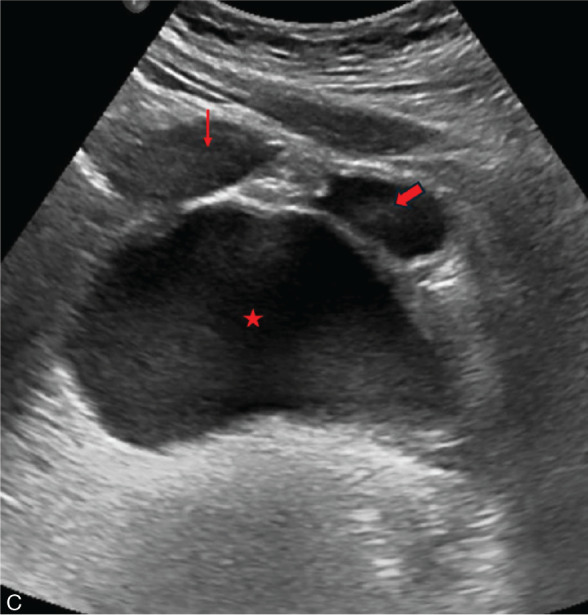

Hematocolpos, characterized by the accumulation of menstrual blood in the vagina, is a rare condition often misdiagnosed due to its uncommon occurrence and non-specific symptoms. Main causes include imperforate hymen, obstructed hemivagina with ipsilateral renal anomaly (OHVIRA), congenital lower vaginal atresia, and complete transverse vaginal septum. Without early diagnosis and treatment, complications such as tubal adhesion, pelvic endometriosis, and infertility can occur. This article reviews the differential diagnosis and treatment of hematocolpos.